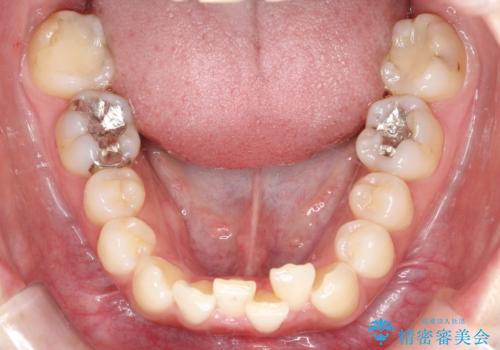

インビザラインで整えた前歯の歯並び

- 患者様は、上下前歯の歯列不正(ガタガタ)を主訴としてご来院されました。治療計画として、透明なマウスピース型矯正装置「インビザライン」を使用し、約2年の期間を見込んで前歯部の歯列を整える方針を立てました。特に下顎前歯に歯肉退縮のリスクがあるため、治療中にIPR(インタープロキシマルリダクション)を行い、歯間を適切に削ることで、過度な圧力を避け、歯肉退縮を防ぎながら配列を進めました。治療は慎重に進め、最終的にきれいで整った前歯の歯並びを目指しました。